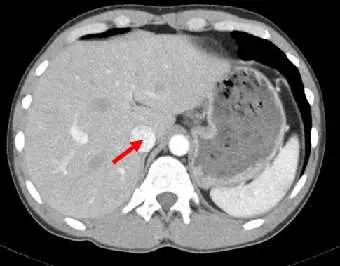

下圖腹部 CT 影像中,箭號所指的構造為何?

此為腹部 CT 軸切面(axial section)影像,對比劑強化掃描。影像中可見:

- 肝臟(liver):右側大片高密度實質器官,密度均勻,為影像主體。

- 脾臟(spleen):左側可見較小的實質器官(影像左上方,密度稍低於肝臟)。

- 脊椎(vertebral column):影像正中央可見高密度骨質結構。

- 紅色箭號所指:位於肝臟右後葉內側、脊椎右前方的橢圓形血管管腔構造,密度低且界線清楚。此位置正是下腔靜脈(IVC)走行於肝後段的典型位置——IVC 嵌入肝臟後方的 IVC 溝(sulcus venae cavae)中,在軸切面呈圓形或橢圓形低密度(或對比增強後高密度)管腔。

影像中箭號所指構造位於脊椎右側、肝臟後葉內側,符合下腔靜脈(IVC)的解剖位置。